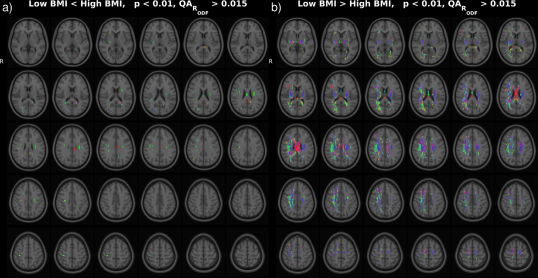

In the HCP dataset, ODFs correlate strongly with the demographic variable BMI. As expected, the ODFs negatively correlate (Fig. 7b) with BMI, indicating a loss of anisotropy with increasing BMI (Fig. 5a,b). This result is consistent with the well-established negative association between global white matter integrity and physical obesity (Mueller et al., 2011; Stanek et al., 2011; Verstynen et al., 2012; Gianaros et al., 2013; Verstynen et al., 2013). The fiber directions (Fig. 8a,b) identified from can be used to perform tractography (Fig. 8c,d). Resulting tracts (Fig. 8c,d) show a pronounced loss of anisotropy in the corticospinal tracts, the optic radiations and the right superior longitudinal fasciculus. These results are corroborated by the existing methods TBSS (Fig. 9a,b, S2a,b), Connectivity-based fixel enhancement (Fig. 9c,d, S2c,d) and local connectometry (Fig. 9e,f, S3a,b). The volume of positive findings of correlation with BMI is largest when using the full ODF information with the ODF approach (Fig. 9). In addition, in a test of specificity, no voxels are found to correlate with randomly permuted BMI (Fig. S4).

Several methods exist to analyze populations of diffusion MRI datasets, typically working on a reduced dimensionality subset of the diffusion data. TBSS (Jbabdi et al., 2010), limiting the analysis to a projection to a tract skeleton, succeeds in identifying the tracts most significantly correlated with BMI (analysis of FA, Fig. 9a,b, S2a,b) but misses the full extent of the correlations. The Connectivity-based fixel enhancement (Raffelt et al., 2015) and Connectometry (Yeh et al., 2016) approaches do include more of the available information and hence perform better than the TBSS method (Fig. 9c,d, S2c,d (Fixel enhancement) and 9e,f, S3a,b (Connectometry) vs 9a,b, S2a,b (TBSS)).

None of the above methods however capitalizes on the full ODF information. This in contrast to the approach presented in this paper. The ODF approach indeed identifies a larger volume of significant findings (227 cm3) than the existing methods tested here (TBSS 17 cm3, Connectivity-based fixel enhancement 15 cm3 and Connectometry 212 cm3, Fig. 9b,d,f,h,j). That is, by analyzing the full ODF information and not reducing the dimensionality of the diffusion data, as is commonly done, the ODF approach is able to pick up on smaller significant changes, better grasping the full extent of the significant findings. Limitations on computational power and diffusion acquisitions (e.g. DTI) which inspired the data reduction of older methods no longer exist. It is hence advisable to maximize the amount of information included in the analysis as in the approach presented here.